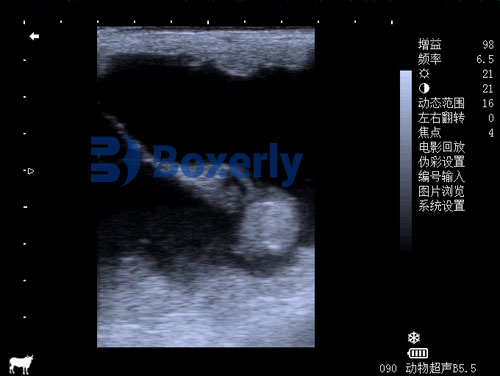

Ultrasound uses sound waves to create images of internal structures. In equine pregnancy detection, a specialized probe is inserted rectally to scan the uterus. The probe sends out high-frequency waves, which bounce off tissues and fluids inside the mare. The returning signals form a picture on the ultrasound screen, showing the veterinarian whether an embryo or fetus is present.

This method is both safe and reliable. It allows the veterinarian to check not only for the presence of pregnancy but also for important details such as the number of embryos, their position, and the condition of the uterus. Over the course of the pregnancy, repeat ultrasounds can monitor fetal development and detect potential issues early.